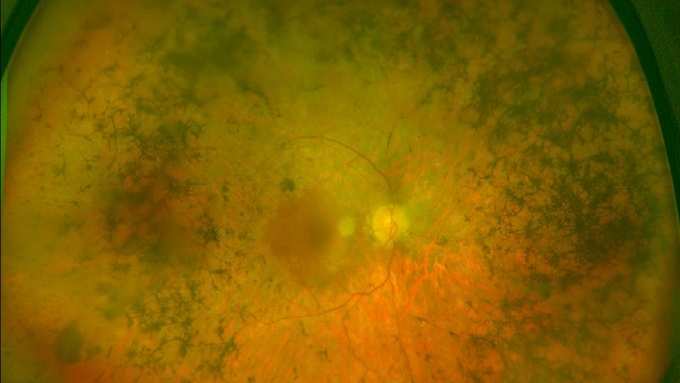

Què és la retinosi pigmentària?

És una patologia hereditària que es caracteritza per la degeneració precoç i progressiva de les cèl·lules retinals, fonamentalment, les fotoreceptores: els bastons (visió nocturna) i els cons (percepció de colors i de detalls), que converteixen la llum en senyals que es transmeten al cervell.

La retinosi pigmentària s’engloba dins del grup de les malalties considerades minoritàries – afecta aproximadament 1 de cada 3.000 persones–, tot i que es tracta de la distròfia hereditària de la retina més freqüent.